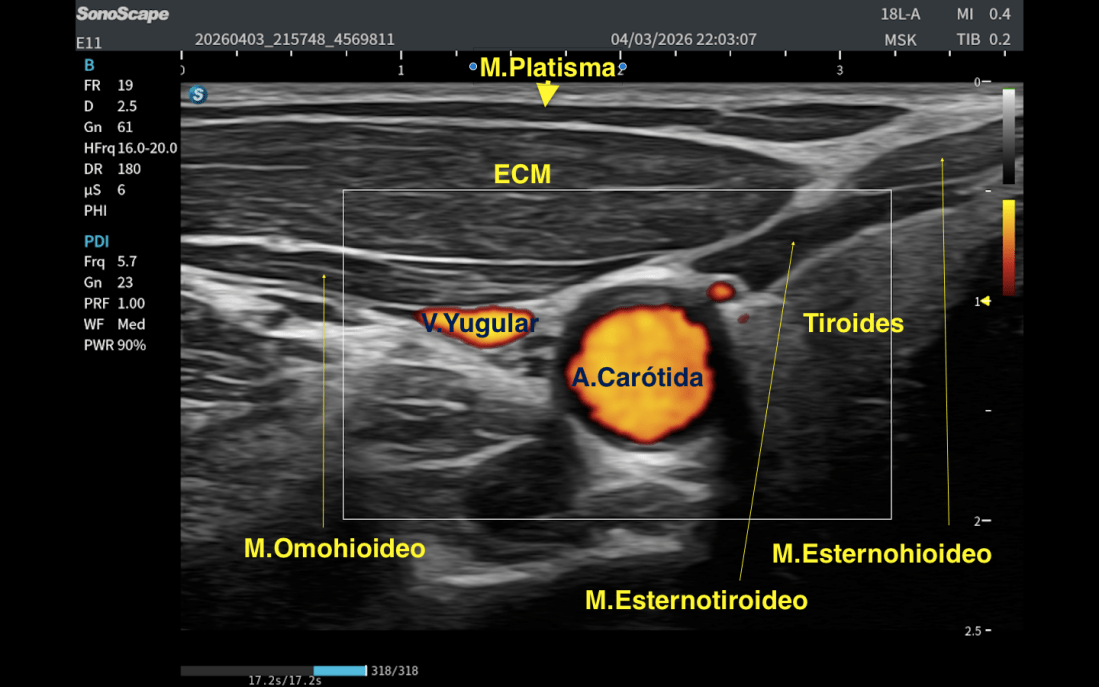

Ahí es donde empiezan a aparecer músculos como:

- El Esternocleidomastoideo ECM

- Los músculos infrahioideos (Omohioideo, Esternohioideo, Esternotiroideo)

- Glándula tiroidea

- Y más profundo aún, el paquete vascular con la carótida y la yugular

Por eso, el Platisma tiene una importancia clave: Marca el límite entre lo superficial y lo profundo en el cuello.